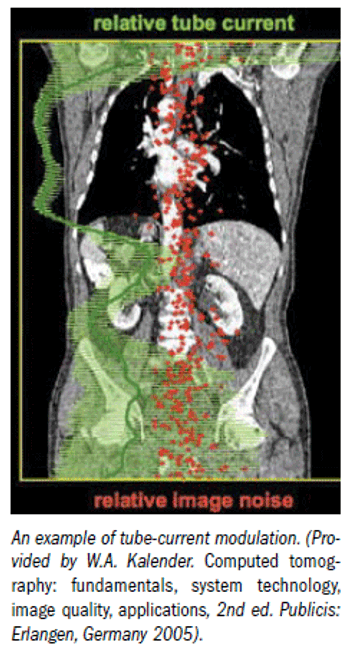

California radiologists will be required to incorporate radiation dose levels in their reports under a measure signed into law Thursday by Gov. Arnold Schwarzenegger. The measure requires that radiologists include in their reports the dose length product or the CT dose index if the machine is able to calculate it.

Because of all the attention currently focused on radiation dose, a California imaging bill addressing radiation exposure has the potential to spread like wildfire to other states. California is a state that doesn’t wait for others to address a problem, so it’s possible similar bills could pop up around the country. The bill has passed the California senate and is now in the California Assembly Appropriations Committee with a hearing set for Aug. 4. Sen. Alex Padilla (D-Pacoima) is lead sponsor of the bill.

The scanner could be brand new, but there is a good chance it's operating with old protocols imported from a previous unit and not optimized for best imaging at the reduced dose levels possible today, a researcher suggests.

If radiologists don't start addressing cumulative radiation history, someone else will do it for them and radiologists won't like the results, according to a speaker at the International Society for Computed Tomography meeting.